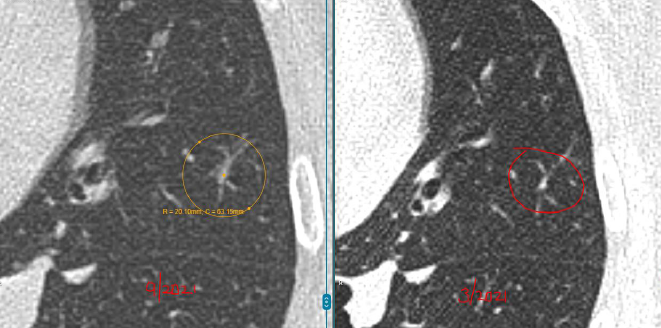

每年复查,她都紧张得睡不着。好在3个结节都一直很“老实”,没变大。可四年后的一次CT复查,让她的心又提了起来:

左肺结节无变化,但右肺的4mm结节密度增高了,还又新添了一颗3mm的磨玻璃结节。

教授指出,右肺那颗4mm的磨玻璃结节虽然密度略有增加,但变化非常小,还不足以判断为恶化。

而左肺的两枚实性结节稳定了三年多,良性可能性超过99%。另外舌叶可见线状影,较前稳定,符合炎性、瘢痕特征。

至于新出现的那颗3mm磨玻璃结节,教授认为它也很“温和”,更像是一种暂时的炎性反应,有可能过段时间就自行消失了。

“这些结节都太小,目前还不到该切的程度,继续观察很安全。”L教授说。他建议孙女士每年复查一次CT,不需要手术、不用活检。

大小和增长速度:超过8mm、短期内明显变大,才值得警惕。

形态特征:边缘毛糙、呈分叶状或伴随血管牵引的,恶性几率高。

时间稳定性:结节在2年以上没有变化,基本可以判定为良性。